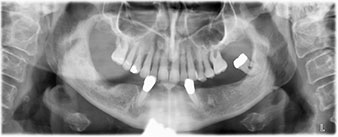

La paciente de 64 años se presentó con una dentición residual compuesta por las piezas dentales 38, 33 y 43 en el maxilar inferior y con una prótesis temporal fijada con ganchos en el maxilar inferior (figs. 1 y 2).

dentición residual

Fig. 1

Fig. 2

El tratamiento periodóntico necesario y la extracción de las piezas en el maxilar superior debía realizarse en un momento posterior, ya que la paciente es profesora y, en el momento de la consulta, estaba ocupada con los exámenes para las pruebas de acceso a la universidad. La paciente no podía comer ni hablar adecuadamente, ya que la prótesis temporal se rompía con mucha frecuencia y con una carga mínima.

Para la planificación y la minimización del riesgo, se realizó una tomografía volumétrica tridimensional (TVD, Planmeca) que mostró que la calidad y la cantidad del tejido óseo era suficiente para la intervención quirúrgica y el tratamiento inmediato con el método Fast & Fixed. Siguiendo el protocolo de este método, se insertaron los implantes en la región de las piezas 35, 32, 42 y 45. Debido a la inclinación de hasta 45 grados de los implantes distales, el perfil de emergencia se desplazó hacia posterior y se generó un mayor polígono de soporte (fig. 3).